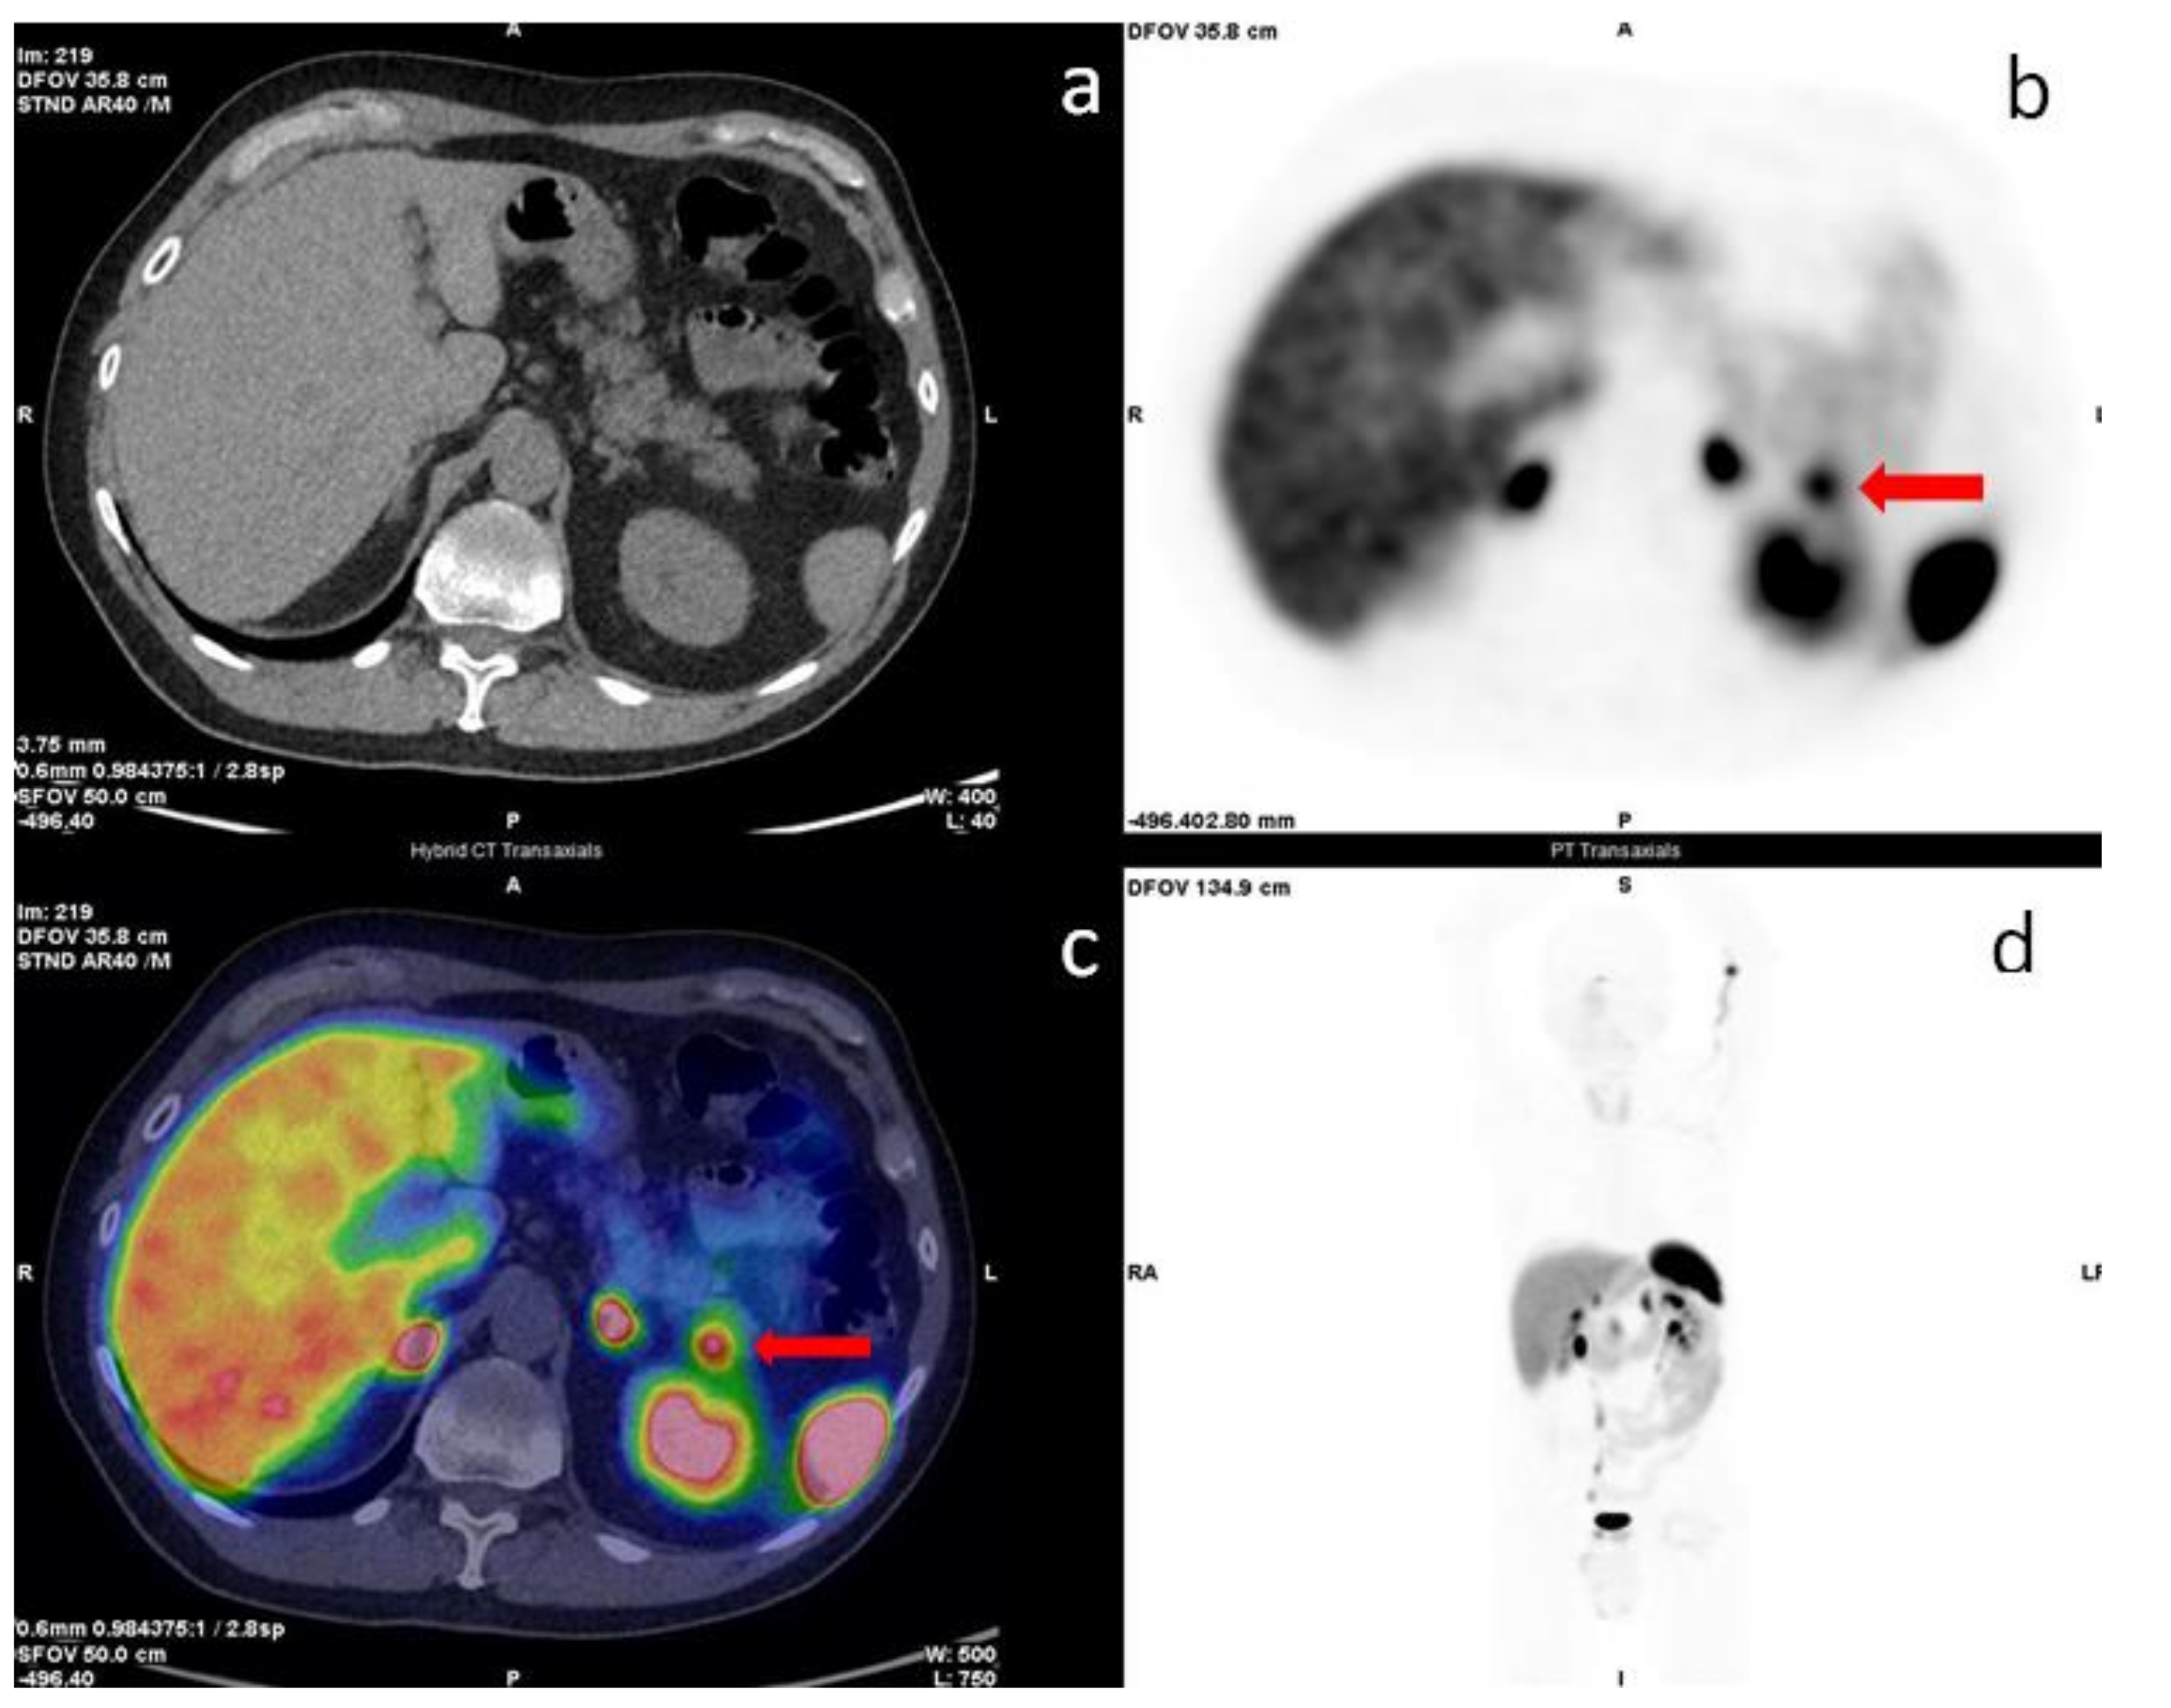

Figure 2.

68Ga-DOTA-TOC PET/CT transaxial images. Low-dose CT: (a), PET: (b), image-fused PET/CT: (c), and maximum intensity projection (MIP) (d). The red arrows in images (b,c) show a focal uptake in the pancreatic tail while restaging patient for small bowel NET (G2, Ki67 3%). The morphological imaging was not decisive for the diagnosis. Cytology revealed accessory intrapancreatic spleen.